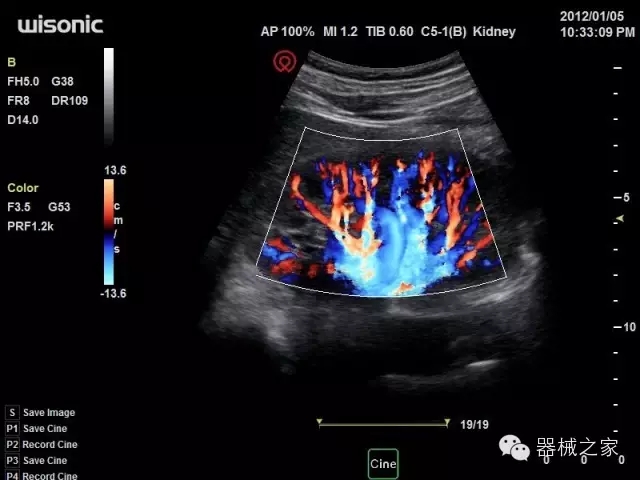

品牌:華聲醫(yī)療(WISONIC)

深圳華聲醫(yī)療技術(shù)有限公司成立于2012年,位于深圳南山西麗湖畔。是一家從事醫(yī)療設(shè)備研發(fā)、制造、營銷的新興高新技術(shù)企業(yè),目前提供生命信息支持、數(shù)字便攜彩超、移動(dòng)醫(yī)療服務(wù)三個(gè)方面的業(yè)務(wù)解決方案。公司核心創(chuàng)始人均為醫(yī)療設(shè)備行業(yè)領(lǐng)軍人物,在醫(yī)療行業(yè)服務(wù)時(shí)間平均在10年以上,對行業(yè)和產(chǎn)品積累了深刻的認(rèn)識。公司在創(chuàng)立之初就有著長遠(yuǎn)的戰(zhàn)略目標(biāo)和規(guī)劃,致力于醫(yī)療設(shè)備行業(yè)的細(xì)分市場,貼近客戶所需,為大眾的健康提供更多關(guān)愛。

官方網(wǎng)站:www.wisonic.cn

經(jīng)典產(chǎn)品:四葉草

臨床圖片賞析

產(chǎn)品特點(diǎn)

·全球目前唯一一款配備主機(jī)雙探頭接口,整機(jī)重量(含電池)在5公斤以內(nèi)的便攜式彩超;

·一款互聯(lián)網(wǎng)彩超,只要有手機(jī)信號的地方就可以非常方便地實(shí)現(xiàn)遠(yuǎn)程會(huì)診和病案調(diào)??;

·鎂鋁合金外殼,堅(jiān)固可靠耐用;

·獨(dú)有的HoloTM PW 實(shí)時(shí)3取樣門PW成像技術(shù),精確進(jìn)行血管診斷;

·一鍵優(yōu)化B、Color、PW,Auto Doppler自動(dòng)識別血管位置、偏轉(zhuǎn)角度等,提高工作效率;

·30°超廣角精細(xì)偏轉(zhuǎn)成像技術(shù),更優(yōu)異的頻譜圖像;

·W+智能搜索引擎,快速尋找圖像;

·SSD、USB3.0保障開機(jī)快,導(dǎo)出圖像更快,減少等待時(shí)間;

·WIFI、網(wǎng)口、3G,多重聯(lián)網(wǎng)方式,全天候保障云端備份,不再擔(dān)心圖像丟失;

CFDA注冊證編號

·粵械注準(zhǔn)201522231208